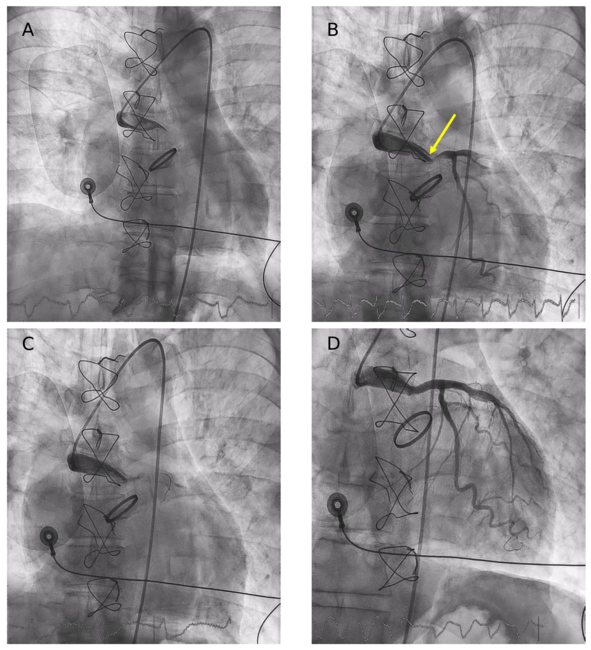

Two years later, he presented to the emergency department with an anterior ST-segment elevation myocardial infarction complicated by cardiogenic shock SCAI (Society for Cardiovascular Angiography & Interventions) stage C. Emergent coronary angiography revealed a subtotal occlusion of the hemi-Cabrol graft caused by a large thrombus, resulting in complete LMCA occlusion. After a challenging catheterization with a 6F JL4 catheter, predilatation was performed using a 2-mm balloon, and 2 overlapping zotarolimus-eluting stents were implanted, followed by partial thromboaspiration because of a residual thrombus (Figure 1, Videos 1-3).